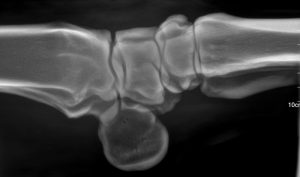

Rayos X Portátil Veterinaria B.S.D. S10 (1 kW) 85Kv

La B.S.D. S10 es una máquina portátil de rayos X veterinaria de 1 kW, diseñada para ofrecer imágenes diagnósticas claras y confiables en todo tipo de escenarios clínicos. Su funcionamiento mediante batería de 24 V DC permite realizar estudios radiológicos en campo, establos, clínicas móviles, emergencias y centros veterinarios, sin depender de una toma de corriente.

Con un rango de 40–85 kV y 1–10 mA, la B.S.D. S10 proporciona la versatilidad necesaria para exámenes de tórax, abdomen, esqueleto y extremidades. Es especialmente valorada en veterinaria equina, donde la movilidad y rapidez de operación son fundamentales.